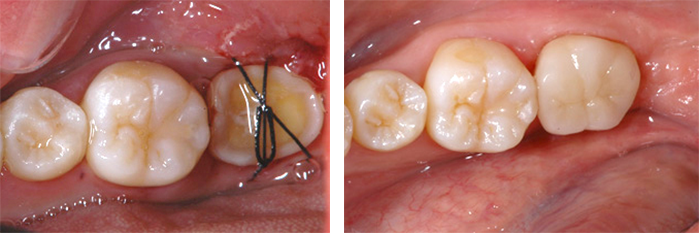

AFTER

移植し歯を固定ました。

移植から一週間後、根の治療をし土台を立て(写真左)、クラウンを被せました。(写真右)。